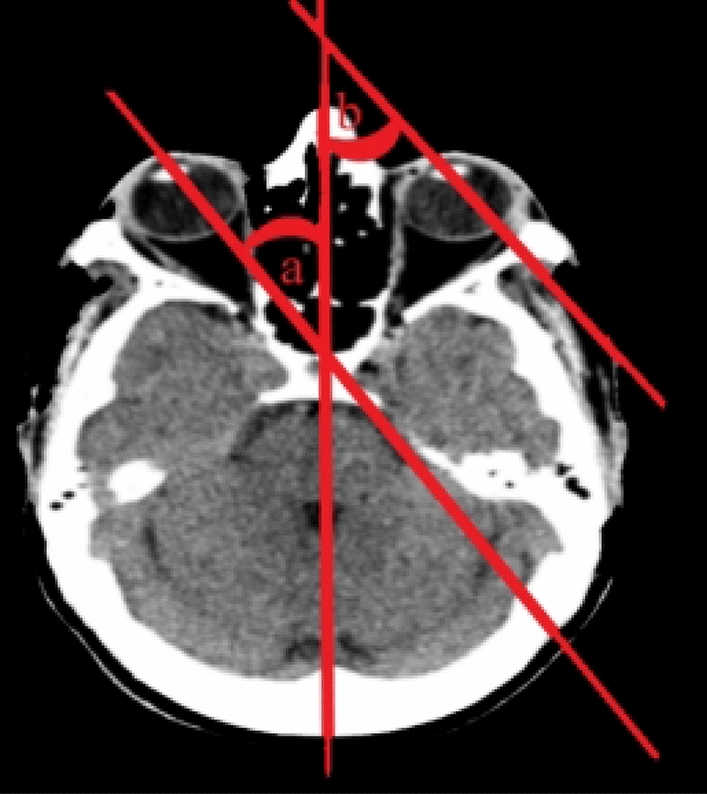

The authors determined the horizontal deviation of eye-in-head position by the using the angle created by the ocular axis's junction with the “line of sight” greatest fit' through the head's midline structures (Fig. 3).

Fig. 3.

The angles formed by the intersection of the ocular axes of the right (a) and left (b) eye and the ‘line of best fit’ through the midline structures of the head were determined